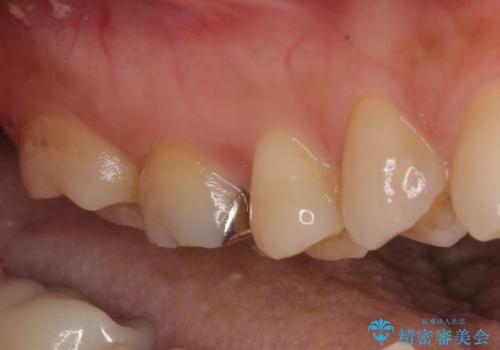

他にも銀歯や欠損となっている歯に対しての治療も希望されたため、補綴治療を行うこととしました。

インプラント治療をきっかけに、銀歯を全てセラミックに替えていきました。